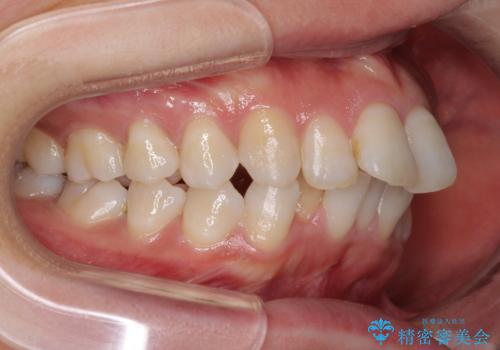

- 上の前歯の飛び出した感じと上下前歯のデコボコを気にして来院された患者様です。

叢生が強く、口元の突出感もあるため、上顎左右第一小臼歯4本を抜歯することとしました。

奥歯の咬み合わせ改善が必要なため、ワイヤー装置による矯正治療を強くお勧めしまたが、本人の希望でインビザラインにて治療を開始することとなりました。